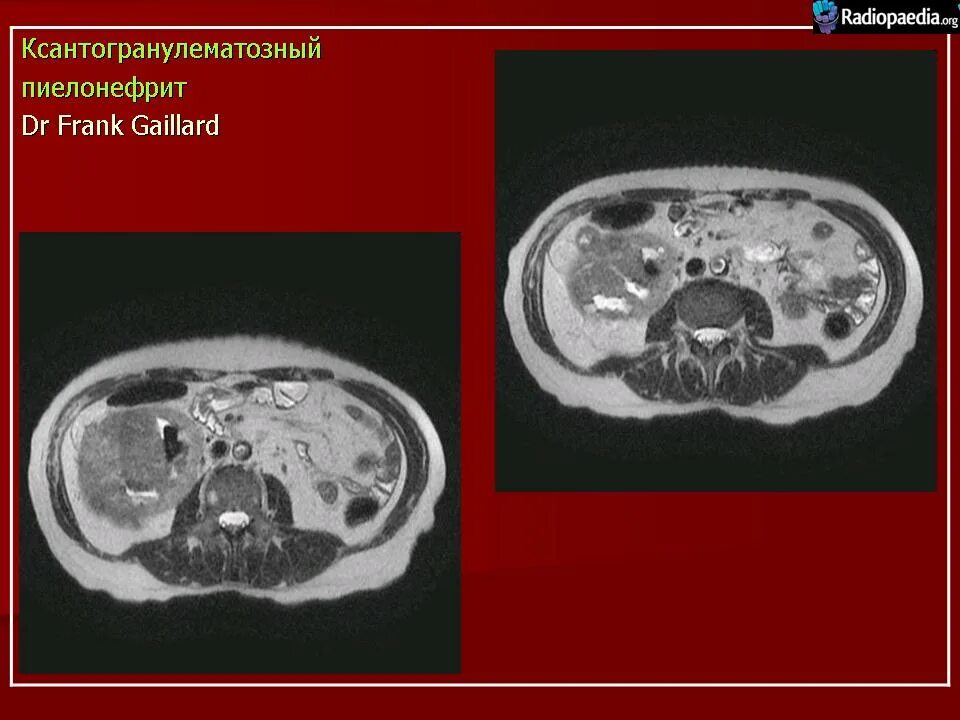

Пиелонефрит кт